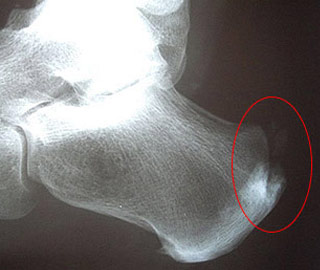

אם הצעדים הראשונים בבוקר גורמים לך כאב בעקב כנראה שהסיבה היא דורבן. כאבים בעקב הינם כאב שכיח ביותר ולמרות שהכאב מיוחס לבליטת עצם הנראית בצילומי רנטגן (במידה ועושים צילום) זו אינה הסיבה לכאב במרבית המקרים. מקור הכאב בקרעים מיקרוסקופים ברקמת …